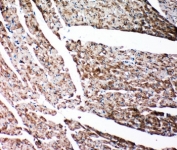

IHC-P: Gelsolin antibody testing of rat heart tissue. HIER: steamed with pH6 citrate buffer.